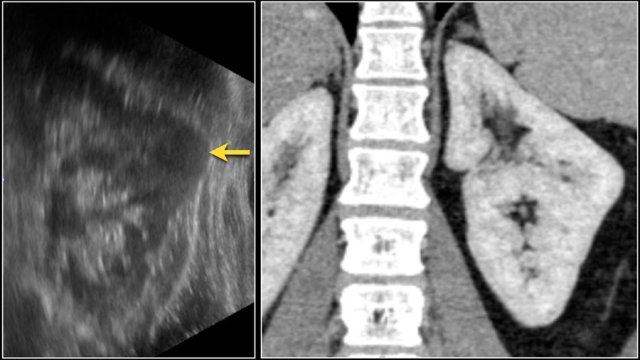

Prominent columns of Bertin, bulging of the renal contour and focal renal hypertrophy can look like a renal mass on ultrasound, unenhanced images and CT in the nephrogenic phase.

In the corticomedullary phase the normal corticomedullary pattern in these pseudotumors can be appreciated, distinguishing them from real lesions.

Suspected renal mass of the left kidney on ultrasound.

CT shows a bulging of the left renal contour, commonly referred to as a dromedary hump.

Here is another case.

In the nephrogenic phase one could argue there is a lesion in the left kidney.

In the corticomedullary phase however it is clear that this is a pseudotumor.